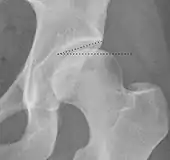

| Crossing ratio | ![]() |

Percentage of acetabular walls crossing. Normal acetabulum is oriented in anteversion. Its value ranges from 15 to 20° in the equatorial plane of the acetabulum and decreases gradually towards the acetabular roof, where normal values range from 0 to 5°. Retroversion of the upper part of the acetabulum has been related with pincer type impingement. In radiography the presence of a "crossover sign" is produced when the posterior wall of the acetabulum crosses the anterior wall before reaching the acetabular roof. It is a sign of acetabular retroversion and it has been linked with overcoverage and pincer impingement. Nevertheless, this sign has been described in 6% of the normal population. Therefore, more important than its presence is the percentage of crossing. | <20%

|